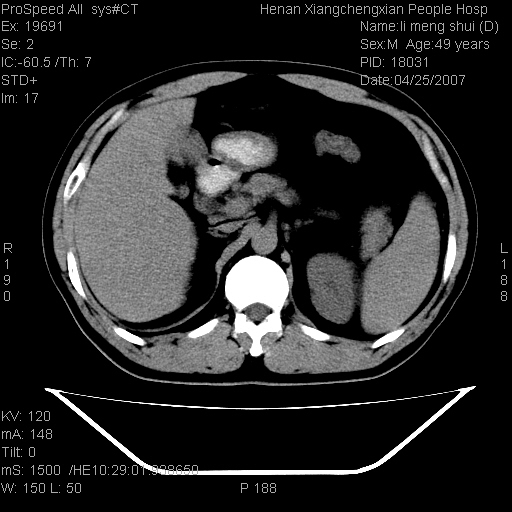

| 患者,男,49岁, 腹疼伴恶心\\呕吐20天,20天前无明显诱因出现右上腹部疼痛,钝疼,无放射,伴恶心\\呕吐,不伴发热.患者不愿增强. b超:肝脏右叶实性占位. ct:肝脏右叶可见一巨块状圆形低密度影,大小约93mm*84mm,其内可见点状高密度影,胆囊、胰腺、脾脏大小、形态及密度未见异常,腹膜后间隙未见肿大淋巴结影。 印象:肝脏右叶巨大肿块,性质待定,建议增强并穿刺活检进一步确诊。 ct平扫: ![]() ![]() ![]() ![]() ![]() ![]() ![]() ![]() ![]() ![]() ![]() ![]() ![]() ![]() ![]() ![]() ![]() 肝脏右叶肿块ct引导下穿刺活检术 患者于16时05分仰卧于ct检查台上,首先行肝脏ct扫描确定进针位置、深度、角度。在局麻下行ct引导下肝脏右叶肿块穿刺活检术。常规消毒、铺巾、局麻。在ct引导下使活检针经右侧腋中线、第9肋间隙垂直胸壁进针90mm,针头进入病变预定位置。在病变预定位置多点、多方向抽取小米样病变组织多块,涂片五张送病理检查。术后穿刺点局部无出血,未出现腹腔积液等并发症。术中及术后患者生命体征稳定,手术于17时10分成功完成。患者安返病房。 穿刺片 ![]() ![]() ![]() ![]() ![]() ![]() ![]() ![]() ![]() ![]() ![]() ![]() ![]() ![]() ![]() ![]() 病理结果肝细胞癌 ![]() 原贴地址:http://www.radinet.com.cn/forum_view.asp?forum_id=4&view_id=24130 ok |